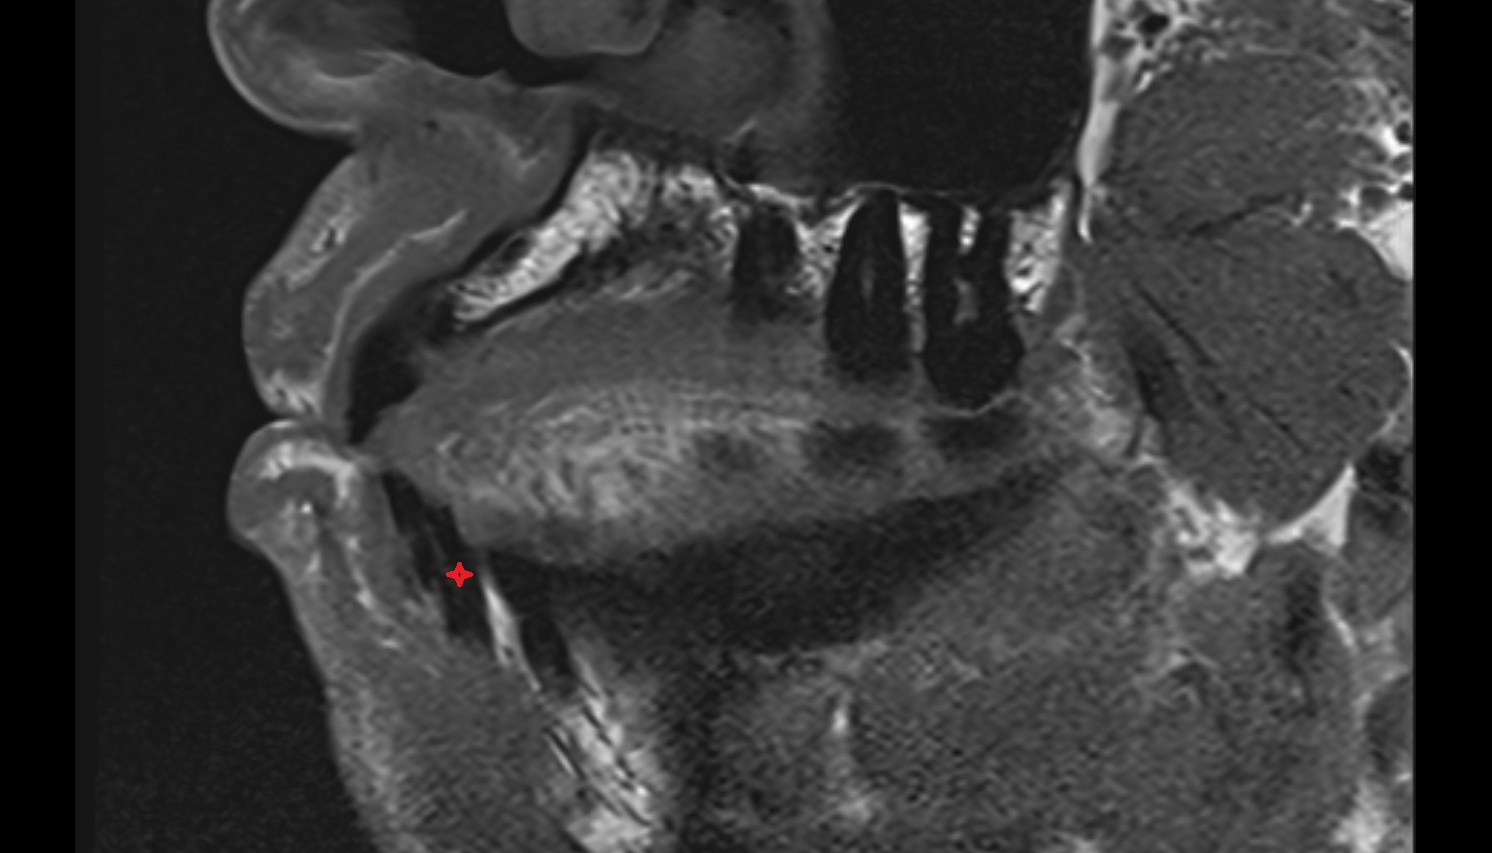

- Articular disc of temporomandibular joint

- Articular eminence

- Articular surface of mandibular fossa

- Temporomandibular joint

- Mandibular condyle

- Mandibular fossa